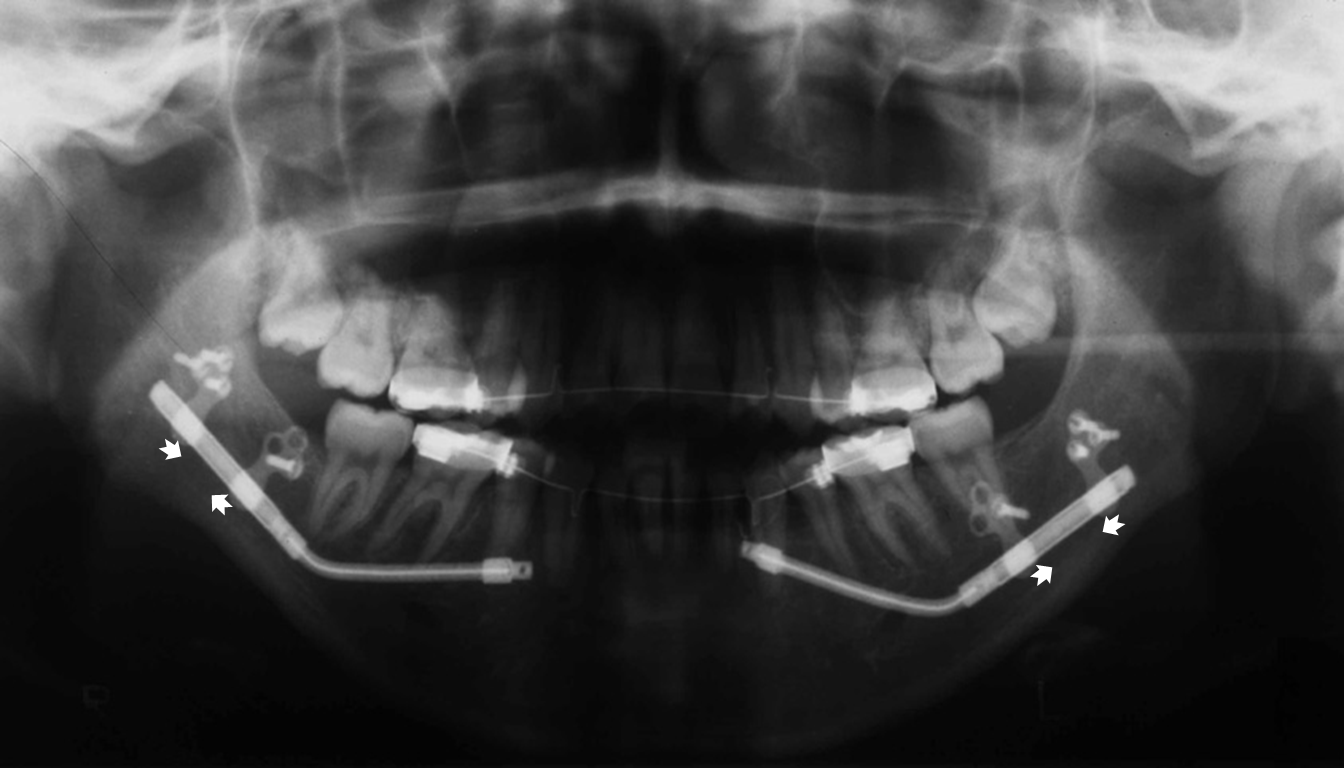

【下顎後退症(骨延長)】

下顎は上顎に比べて成長が小さく後退しており、咬合は開咬を呈し下顎の後退も認められます。

一般的には下顎を前方に移動し一期的に咬合を構成する下顎前方移動手術を行いますが、このような従来の方法では術後に再び咬合の異常が発症する”後戻り”を起こす危険性が高く、さらに顎関節の異常な吸収を引き起こす可能性が指摘されております。そこで下顎骨の骨延長を適用しました。

術中写真

術後パノラマX線写真

骨延長器装着後8日目より、1日2回(朝・夕)0.5mm/回骨延長し、最終的には右7.0mm、左9.5mmの延長が得られました。口腔内に露出する延長装置の周囲のケアを担当歯科衛生士が行います。 骨延長終了後6カ月には延長部の新生骨は成熟骨になり、この時期に骨延長装置を除去します。

骨延長後6カ月口腔内写真

骨延長6カ月後パノラマX線写真

術後矯正歯科治療を行い、機能的な咬合が完成します。手術前に認められた咬合の異常や下顎の後退は改善しております。